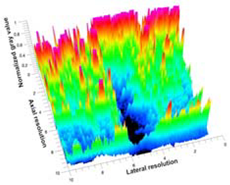

3.5. Echogenicity

| Aerogel Type | US Image | Normalized Intensity Map | 3D Intensity Map | |

| 1 | Muscle |  |  |  |

| 2 | X-silica |  |  |  |

| 3 | X-silica-La2O2S:Eu |  |  |  |

| 4 | SMPU-Mix-14 |  |  |  |

| 5 | SMPU-Mix-18 |  |  |  |

| 6 | BRF-CA |  |  |  |

| 7 | ARF-CA |  |  |  |

| 8 | X-Ca-Alg-2 |  |  |  |

| 9 | X-Ca-Alg-1 |  |  |  |

| Aerogel Type | Imaging Frequency (MHz) | Optimal Frequency (MHz) | Echogenicity | Image Characteristics | Impedance Mismatch (%) | |

| X-silica | 6.5–13.4 | 13.4 MHz | Hypoechoic | Least Hyperechoic | Distinct linear boundary | 92.03 |

| X-silica-La2O2S:Eu | 6.5–13.4 | 13.4 MHz | Hypoechoic | Least Hyperechoic | Distinct linear boundary | 90.28 |

| SMPU-Mix-14 | 6.5–13.4 | 11 MHz | Hyperechoic | Moderately Hyperechoic | Irregular boundary | 98.33 |

| SMPU-Mix-18 | 6.5–13.4 | 11 MHz | Hyperechoic | Moderately Hyperechoic | Irregular boundary | 98.23 |

| BRF-CA | 6.5–13.4 | 13.4 MHz | Hyperechoic | Hyperechoic | Waterfall appearance | 97.16 |

| ARF-CA | 6.5–13.4 | 13.4 MHz | Hyperechoic | Hyperechoic | Waterfall appearance | 97.12 |

| X-Ca-Alg-2 | 6.5–13.4 | 11 MHz | Isoechoic | Strongly Hyperechoic | Irregular boundary | 98.03 |

| X-Ca-Alg-1 | 6.5–13.4 | 11 MHz | Isoechoic | Strongly Hyperechoic | Irregular boundary | 97.97 |